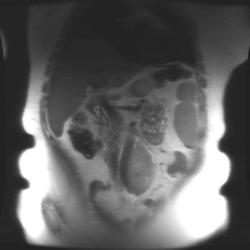

Женщина 47 лет, в течении долгого времени страдала от головных болей. В последние несколько месяцев - прогрессирующая потеря зрения (на оба глаза).

Presented images are corresponded for cerebral (right temporal-occipital region) neoplasia; high grade glioma is most suggested.

Глиальная опухоль.